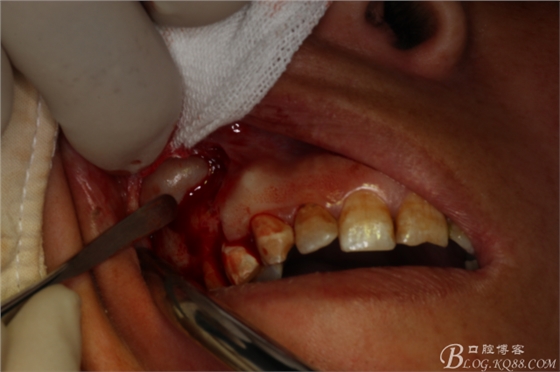

圖9.暴露出16根尖上方的囊壁

圖10.完整摘除囊壁